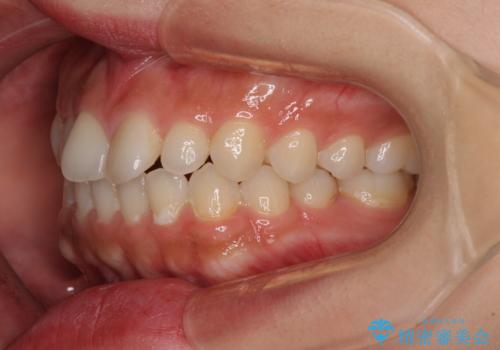

インビザラインを用いた上顎の部分矯正

- 上顎前歯の叢生を気にして来院された患者様です。

下顎前歯や上下奥歯の咬み合わせには殆ど問題がないため、上顎前歯のみを矯正する治療を提案しました。

ワイヤー装置でもインビザラインでも可能でしたが、前歯のみをきれいに排列するのであればインビザラインの方が仕上がりが良いので、インビザライン・ライトにて治療を行うこととしました。